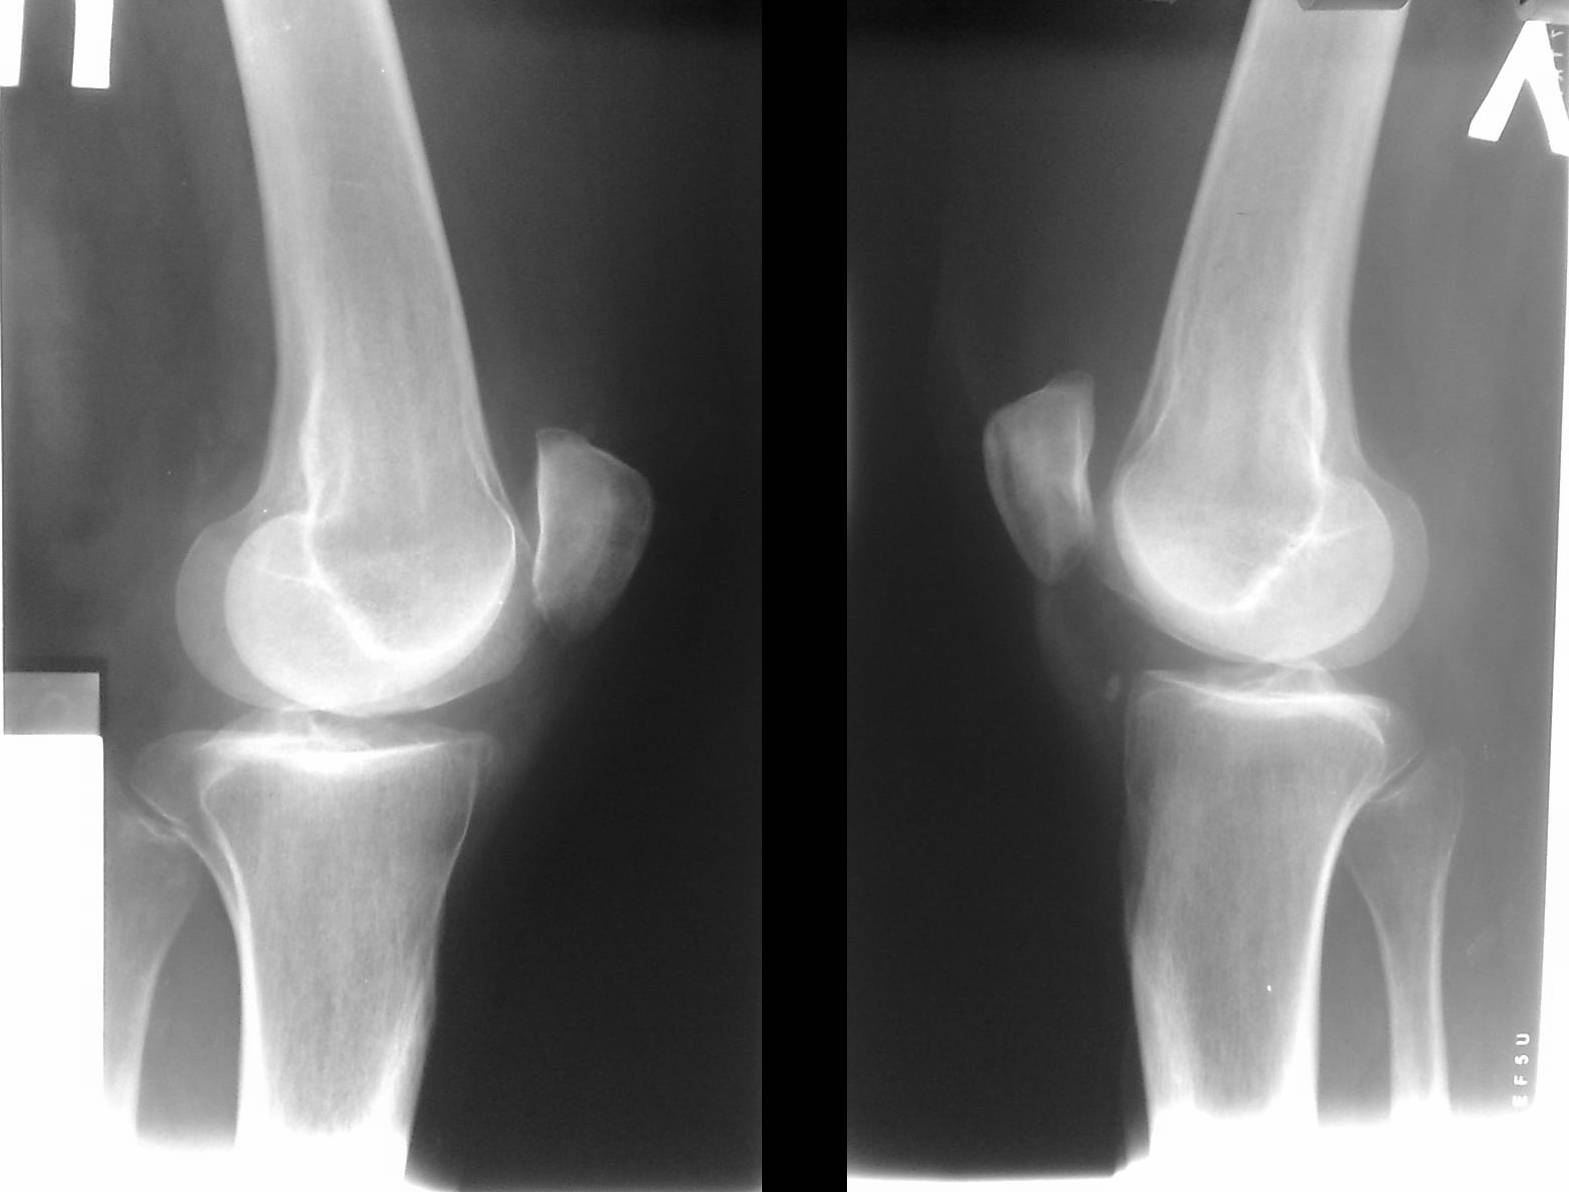

• 1 стадия. Дискомфорт и неясные незначительные боли без четкой локализации. На рентгенограмме выявляется овальное некротизированное тело, отделенное полоской просветления от здоровой кости.

• 2 стадия. Умеренные боли в суставе, явления синовита. Полоса просветления на рентгеновских снимках становится шире. Целостность замыкательной пластинки на поврежденном участке нарушается.

• 3 стадия. Боли, похрустывание и «заедание» сустава. Возможны блокады. На рентгенограммах выявляется некротизированный участок, частично отделившийся от кости.

• 4 стадия. Боли усиливаются, однако блокады становятся более редкими. Отмечается нарастание синовита. На рентгеновских снимках обнаруживается полностью отделившееся внутрисуставное тело.

Диагноз выставляется на основании истории болезни, жалоб пациента, данных физикального обследования и дополнительных исследований. Самым доступным, недорогим и, как следствие, популярным способом инструментальной диагностики является рентгенография. В ряде случаев участок некротизированной кости виден на рентгенограмме. Однако следует учитывать, что область некроза невелика в ряде случаев может не отображаться на снимках. Поэтому отсутствие изменений на рентгенограмме не является основанием для исключения диагноза рассекающий остеохондрит.